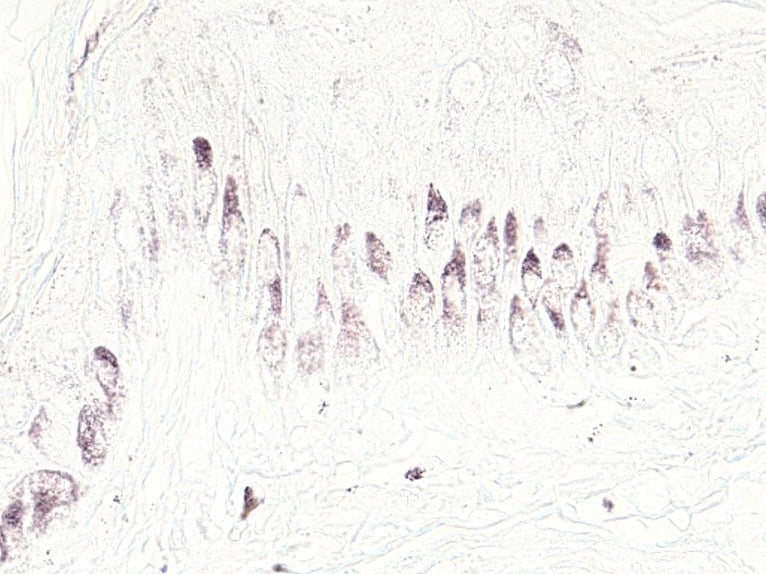

STUDY ON MELANOCYTES

To evaluate our patented technology Dendrix®, we conducted a study directly on melanocytes, the skin cells responsible for pigmentation. Under UV exposure, these cells normally extend dendrites that transfer melanin to surrounding skin cells.

With Dendrix®, dendrite growth was reduced by 44 percent compared to untreated cells. This result demonstrates a lower melanin transfer and a visible reduction of pigmentation at its source.

AFTER

Melanocytes under UV with Dendrix®

AMOUNT OF MELANIN IN SKIN LAYER

These images from our skin explant study illustrate the presence of melanin in the epidermis. On the left, the colored patches show melanin cells after UV exposure without any treatment. On the right, melanin is shown after UV exposure with our product, MELANCLAIR Emulsion Concentrate A. A significant reduction in melanin cells can be clearly observed, highlighting the efficacy of our product.